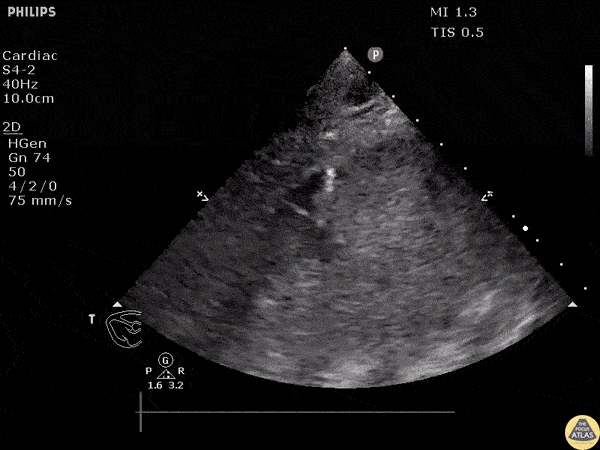

Patient had PEA arrest. View of the heart revealed pericardial effusion. The needle entering the pericardium can been seen in this clip. Image courtesy of Robert Jones DO, FACEP @RJonesSonoEM Director, Emergency Ultrasound; MetroHealth Medical Center; Professor, Case Western Reserve Medical School, Cleveland, OH View his original post here